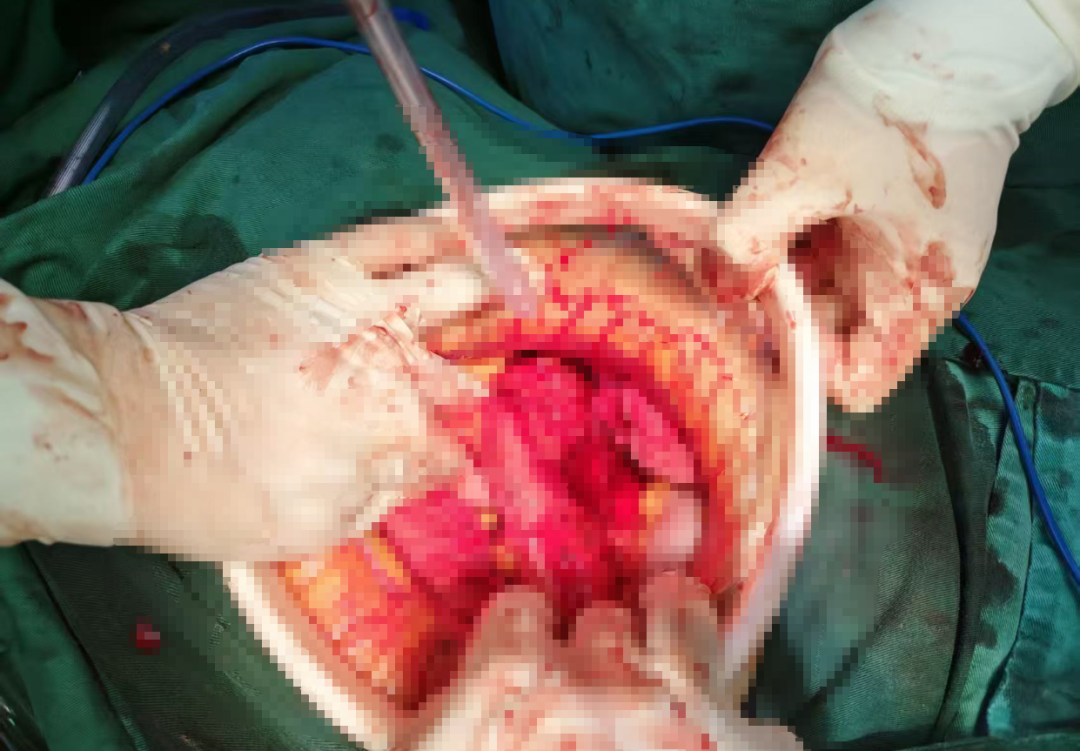

术中,见腹腔内积聚大量鲜红色血液及血凝块,但未见消化液泄漏。团队果断启用自体血回输技术,将出血收集、过滤、清洗、净化后安全回输,既争分夺秒又节约血源。在清除了约2500毫升的积血与血块后,真正的“破裂点”终于浮出水面:降结肠系膜血管破裂,周围组织严重毁损,一段约7厘米的降结肠呈“袖状”撕脱。血肿范围广泛,向内累及腰椎旁,向外达左肾外侧,上至胰腺下缘及脾脏,下抵盆腔,损伤范围之大,让手术难度陡增。

面对复杂局面,胃肠外科主任朱惠东带领手术团队沉着应对,对多处出血点进行精细缝扎,运用止血纱填塞创面,并反复冲洗腹腔,在确认无任何活动性出血后,为患者施行了损伤结肠切除+降结肠造口术。手术历时数小时后顺利完成。